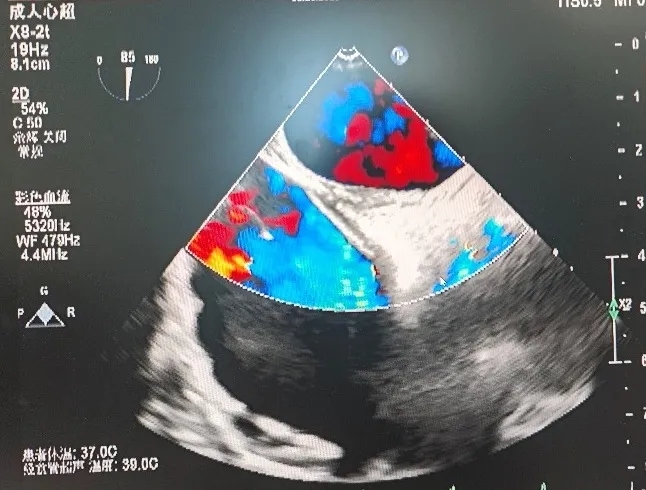

超声所见:经食管超声心动图+灰阶三维成像+彩色三维成像:卵圆孔未闭可吸收封堵器置入术后6个月:可吸收封堵器位置固定,未见残余分流,可吸收封堵器与房间隔自身组织贴合紧密,变薄,其回声与心肌组织回声接近,右房面可见封堵器的条状回声反射。

超声结论:经食管超声心动图+灰阶三维成像+彩色三维成像:卵圆孔未闭可吸收封堵器置入术后6个月:可吸收封堵器回声与心肌组织回声接近,未见残余分流。

超声所见:经食管超声心动图+灰阶三维成像+彩色三维成像:卵圆孔未闭可吸收封堵器置入术后:未见残余分流,可吸收封堵器位置回声与心肌组织回声接近。

超声结论:未见残余分流。